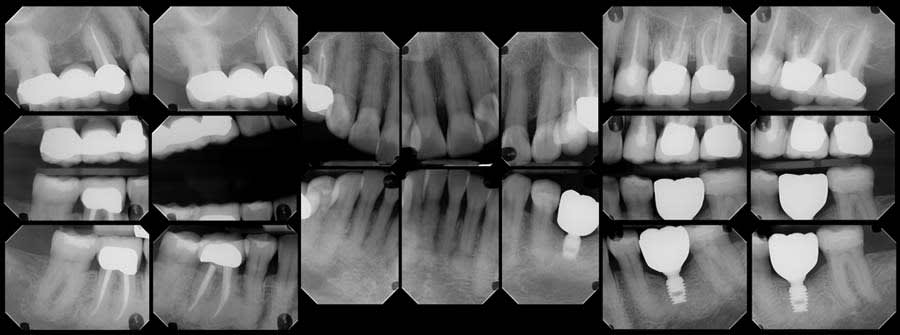

This study received exemption from the Institutional Review Board of Midwestern University College of Dental Medicine-Arizona. A 62-year-old female patient presented for her 6-month recare cleaning, examination, and full-mouth series x-rays (FMX) in 2025. Oral cancer screening was completed for extra- and intraoral lesions with results within normal limits. Clinical examination revealed a full complement of dentition with the exception of teeth Nos. 3, 19, and all third molars. Tooth No. 19 had an endosseous implant that was fully restored. Right mandibular dentition were free of caries with resin restorations on teeth Nos. 29 and 31 and a nonsurgical root canal with a porcelain-fused-to-metal crown on tooth No. 30.

Upon review of the FMX, multiple quadrants of hypercementosis were noted, including all mandibular quadrants and the maxillary left quadrant, and an electric pulp test of the mandibular right posterior quadrant demonstrated vital pulps, with the exception of tooth No. 30 (Figure 1). Teeth Nos. 29 and 30 had no mobility and were percussion negative with periodontal pocket depths buccally of 3 mm and 2 mm and distally of 3 mm and 4 mm, respectively. There was no pain on percussion of tooth No. 31. From the periapical radiographs, the roots of teeth Nos. 29 and 30 were noted to be grossly thickened, bulbous, and blunted due to a fairly symmetrical deposition of a radiopaque material on their surfaces (Figure 2, right). Also noted, both the second premolar and first molar had obvious concrescence of cementum, most pronounced at the first molar (Figure 2, right). In addition, tooth No. 30 incipient PDL space widening and generalized posterior alveolar osseous bone loss were also noted.

To establish a differential diagnosis, in addition to testing both teeth Nos. 29 and 30 for endodontic/periodontal disease, the clinician reviewed the patient’s systemic health and referenced a previous FMX captured in 2018, which demonstrated a progression of cementum deposition (Figure 2, left). Cementum deposition progression to concrescence of Nos. 25/26 could also be noted (Figure 3).

A review of the patient’s dental history revealed that she was never diagnosed with periodontitis, and bone loss had been attributed to physiological aging, gingival recession, and increased biomechanical loading. Tooth No. 19 had been extracted due to secondary caries and not periodontal conditions. The 2018 FMX exhibited generalized hypercementosis, including the mandibular right, mandibular central, and maxillary left posterior areas, and no evidence of concrescence (Figure 4). In 2022, the patient had a cone-beam computed tomography (CBCT) scan in preparation of the No. 19 implant where hypercementosis with concrescence could be seen with Nos. 25/26 and 29/30 (Figure 5).